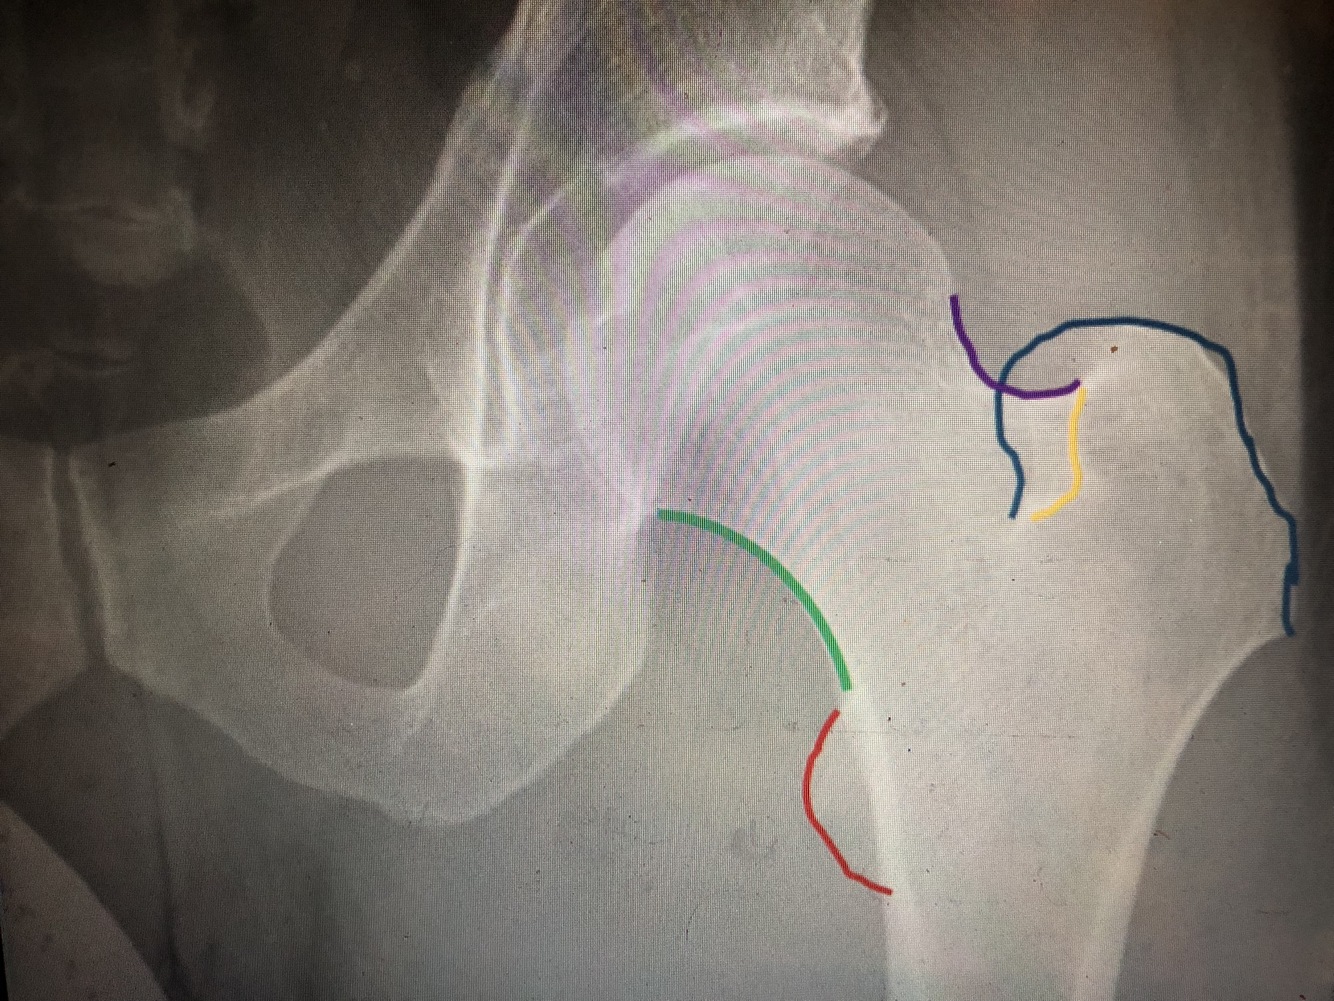

What is the blue line/#3?

secondary compressive trabeculae

What is the yellow line/#2?

primary tensile trabeculae

What is the blue area/#4

Ward’s triangle is the relatively trabeculae-free area

What is the dark blue line?

Kohler’s teardrop

What is the purple line?

greater trochanter

What view is this?

Frog leg

What is the light blue line?

lesser trochanter

What is the yellow line?

intertrochanteric crest